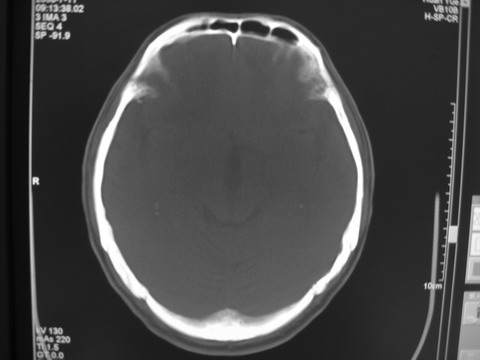

患者 男 69岁 头晕头痛不适

多发病灶,指状水肿,首先诊断转移瘤。

多个结节并周围大面积水肿区,多考虑多发性脑转移瘤

小病灶、大水肿,病灶多发,首先考虑多发转移瘤;建议查原发灶。

额顶叶多发小病灶、大水肿,首先考虑多发转移瘤;建议查原发灶

脑内多发病灶,小病灶,大水肿。

典型转移性肿瘤。

应进一步检查,查找原发病灶。

结果 : 该患者结肠癌病史5年 考虑脑转移